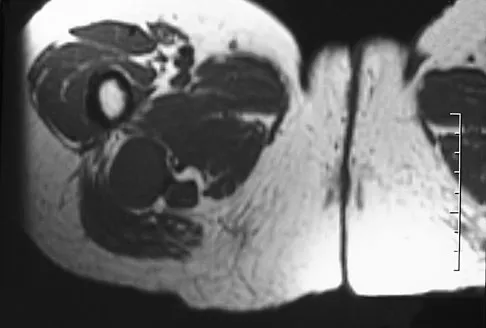

A patient has right shoulder pain. Figure 1a shows a gadolinium-enhanced transverse MRI scan at the level of the coracoid. Figure 1b shows an arthroscopic view of the anterior structures from a posterior portal. These images reveal which of the following findings?

The area shown in the arthroscopic view and MRI scan is referred to as a Buford complex and represents a normal labral variant. It consists of a thickened, cord-like middle glenohumeral ligament, a superior labral attachment of the middle glenohumeral ligament just anterior to the biceps tendon, and absence of the anterosuperior labrum. This combination of findings can be confusing and may simulate labral pathology. Mistaken repair of the lesion back to the glenoid rim can result in significant loss of external rotation. A Bankart lesion would be located at the inferior anterior glenoid rim. The subscapularis is seen anterior to the labrum. Normal variations that occur in the anterosuperior labrum can simulate pathology. Gusmer PB, Potter HG, Schatz JA, et al: Labral injuries: Accuracy of detection with unenhanced MR imaging of the shoulder. Radiology 1996;200:519-524. Griffin LY (ed): Orthopaedic Knowledge Update: Sports Medicine. Rosemont, IL, American Academy of Orthopaedic Surgeons, 1994, pp 47-63.